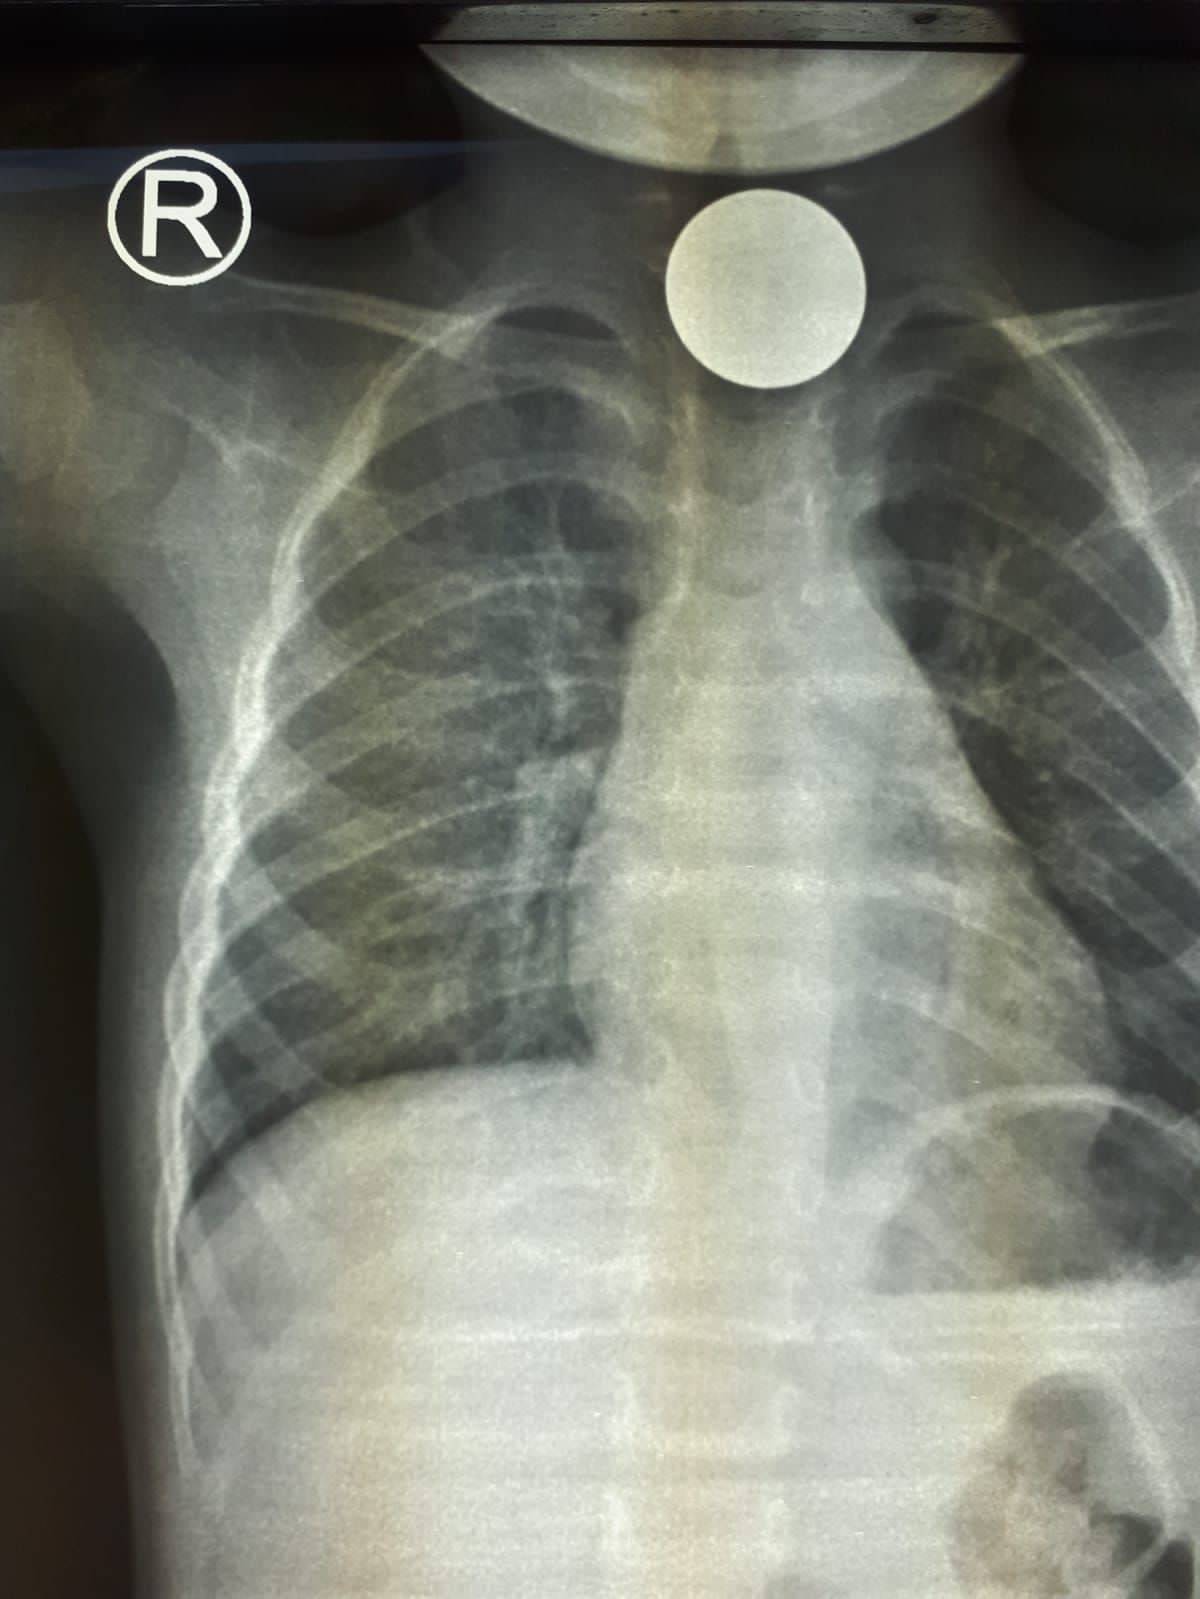

فريق طبي بـ "رابغ العام" يستخرج قطعة معدنية من بلعوم طفل في عمر السنتين

تمكن - بفضل الله - فريق طبي بمستشفى رابغ العام من استخراج قطعة معدنية من بلعوم طفل يبلغ من العمر عامان خلال عملية لم تستغرق أكثر من 10 دقائق.

وأوضحت (صحة جدة) أن الطفل قَدِم إلى طوارئ المستشفى وهو يشكو ابتلاع جسم غريب (قطعة نقود معدنية) كانت قد علقت في منطقة البلعوم؛ مما تسبب في اختناق وعدم قدرة على البلع؛ حيث قرر الطاقم الطبي إجراء عملية عاجلة بالمنظار لإزالة الجسم الغريب، والتي تبين أنها قطعة معدنية نقدية، وقد كُللت العملية بالنجاح دون حدوث مضاعفات - ولله الحمد - وقد غادر الطفل المستشفى وهو بصحة جيدة.